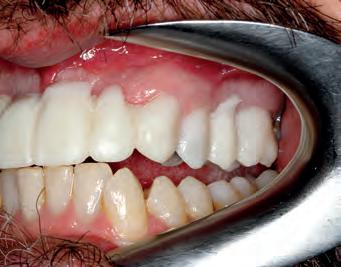

TOP LEFT: Trial smile face RIGHT TOP: Trial smile close up RIGHT BELOW: Trial smile retracted front BOTTOM ROW LEFT: Trial smile retracted left BOTTOM ROW RIGHT: Trial smile retracted right

A digital smile design film was made with 3Shape Dental Designer. This gives a much better illustration. We chose to include the design also for UR54 for better cosmetic effect, even though the patient didn’t seem to be that concerned about treating UR54 after the temporary bridge solved his immediate problem. The patient liked the digital design, because it didn’t just ‘show teeth’, but it showed a simulation of teeth superimposed onto the patients face. From experience patients find this very helpful, instead of just looking at a design of teeth.

A printed model was produced on a Structo Dentaform 3D printer, a clear silicone stent was made to ‘glue in’ the trial smile, and show the patient what it would look like. The patient liked it so much, that he decided to include UR5,4 after all.

The trial smile was used as a prep though guide and photos were taken for stump shades (ND3). New temporaries were made in B1, and the patient did not want any changes made, to the temporary trial smile. A further scan and photos were made, to give the technician as much information of the process. I know he appreciates and it helps us both to produce a better result.